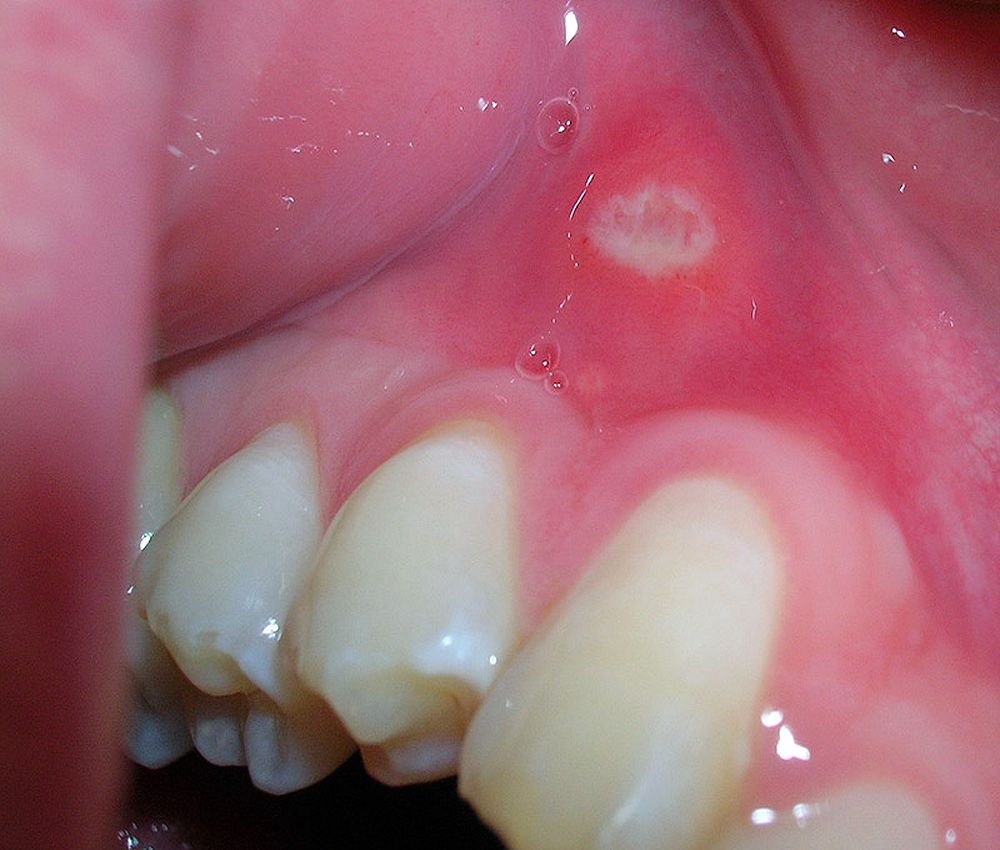

1. Gingivitis descamativa

Se caracteriza porque se produce la separación de las capas externas de las encías dejando incluso la raíz del diente expuesta, provocando sensibilidad ante agentes externos como bebidas o comida caliente o fría.

La gingivitis descamativa hace que el tejido gingival se enrojezca, duela e incluso pueda aparecer sangrado, ya sea espontáneo o al cepillar los dientes.

Esta patología, debe de tratarse a tiempo ya que, de no ser así, puede derivar en una periodontitis, una enfermedad más grave y difícil de curar que provoca la caída de los dientes.

Por todo esto, te recomendamos tener un control del estado de las encías, esto, conlleva ir al dentista en cuanto se observe los síntomas mencionados anteriormente.